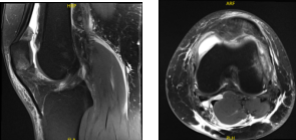

The patient also presented an MRI result that showed findings in keeping with recent transient lateral patellar dislocation with impaction contusions of the inferomedial patella and anterolateral distal femur. Partial tearing at the patellar attachment of the medial retinaculum. Moderate joint effusion. Partially ruptured popliteal cyst.

MRI Left Knee non-contrast